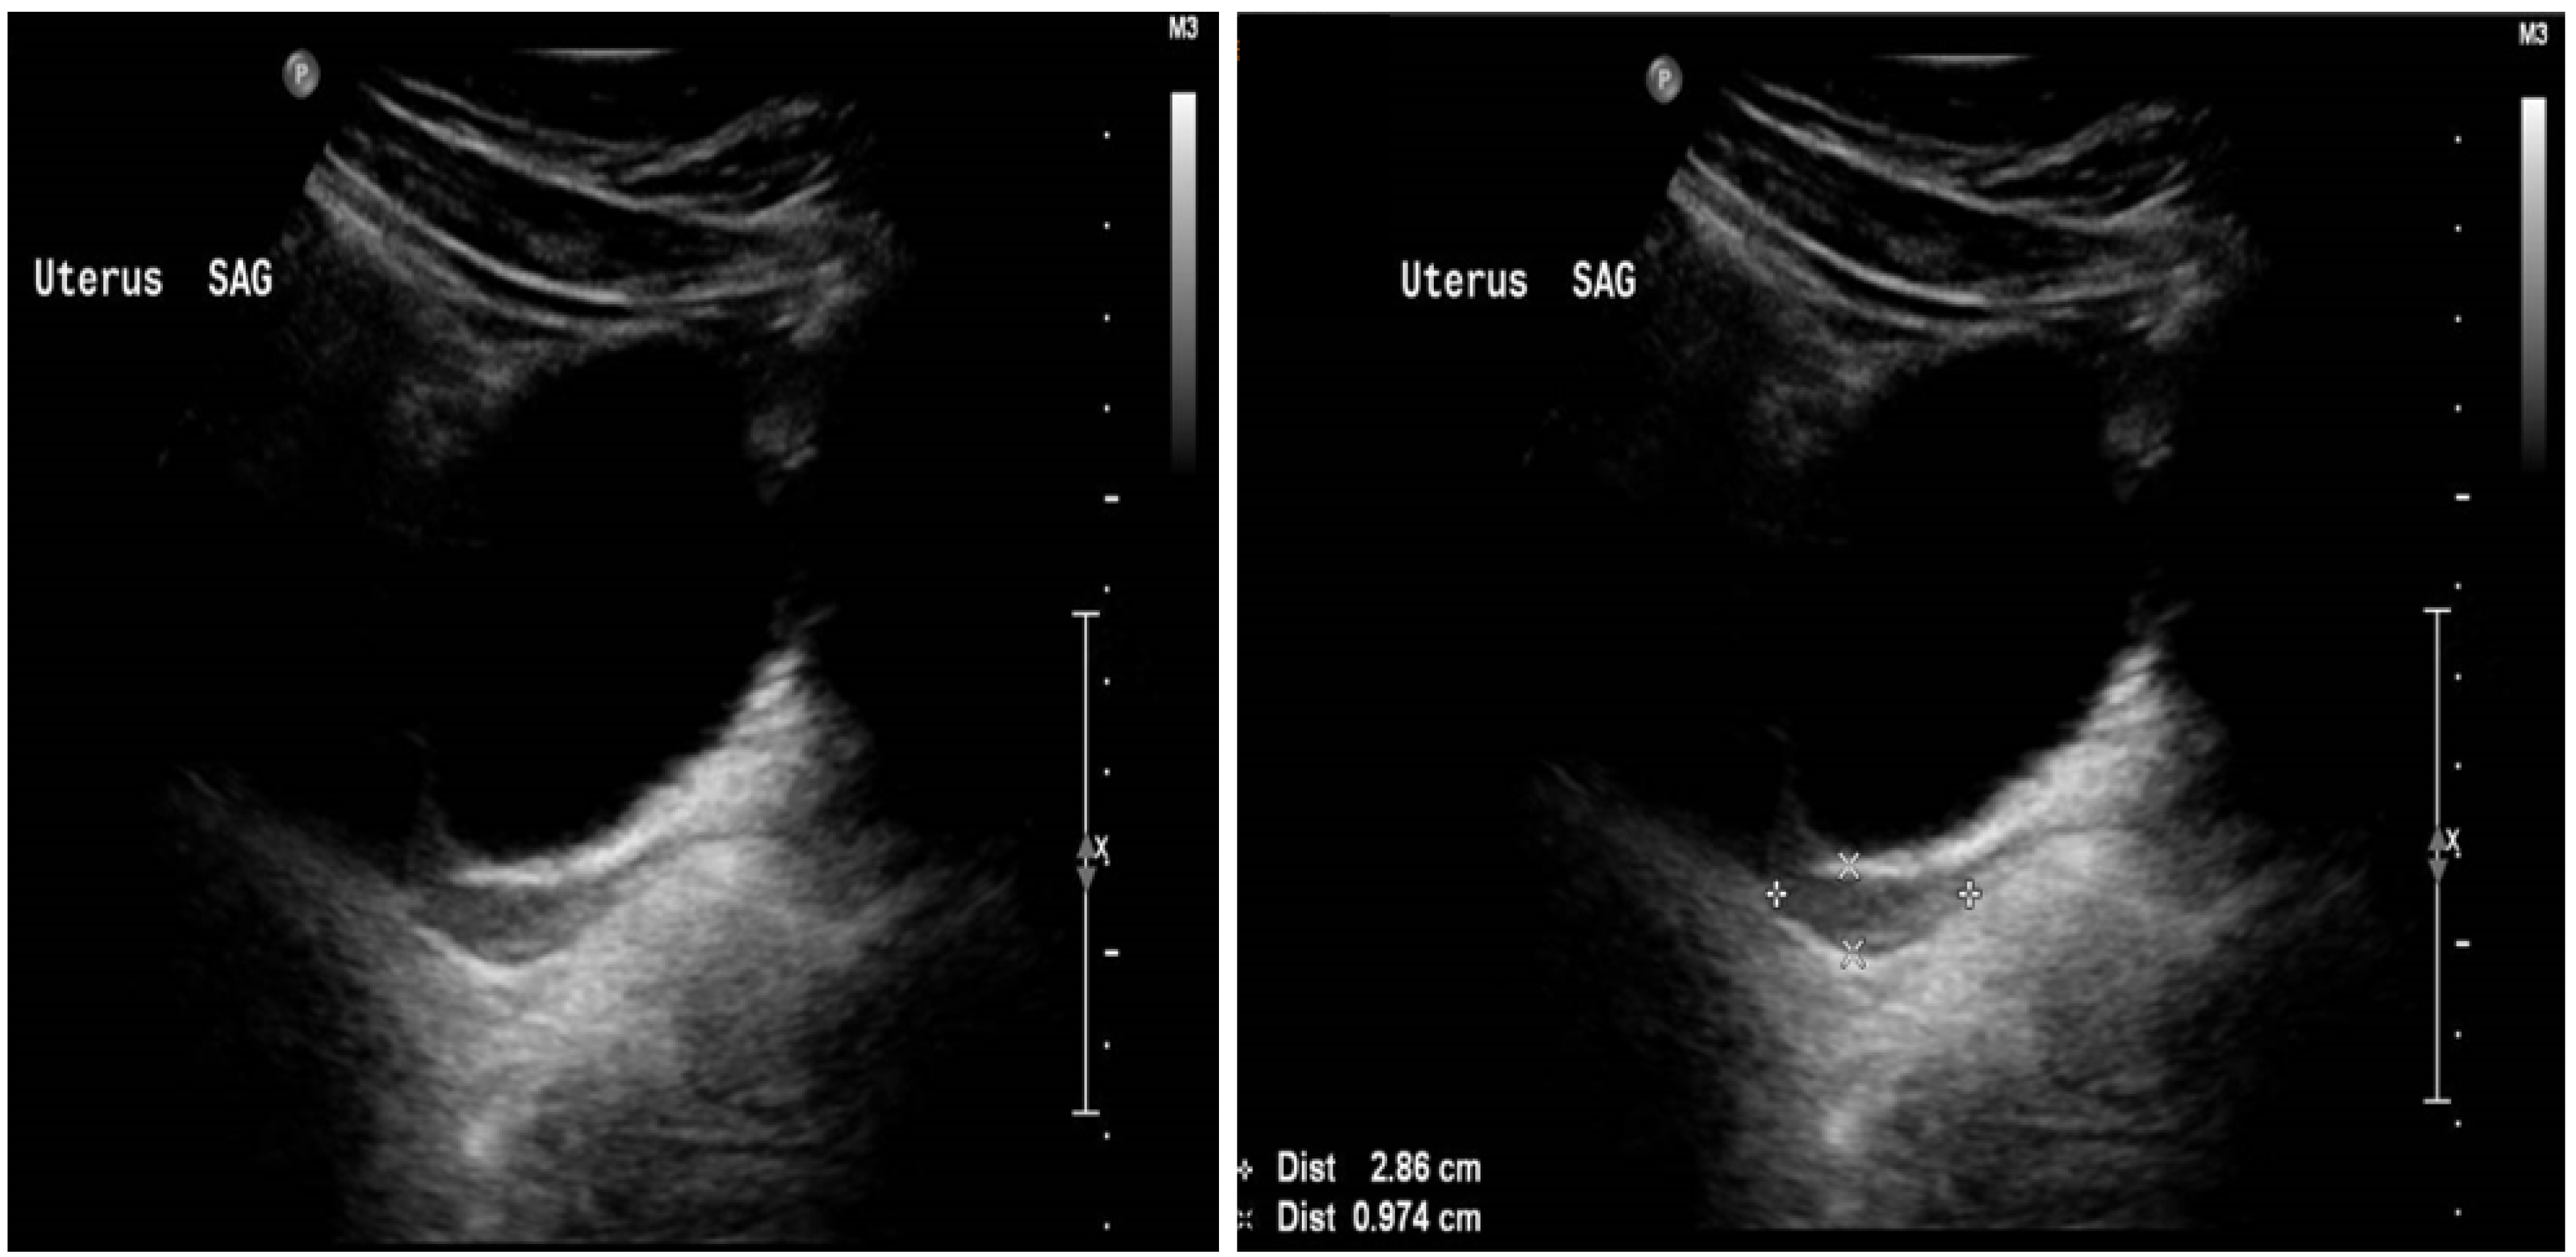

2. Case Report